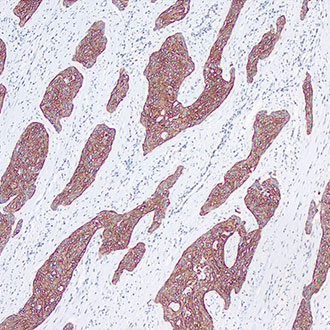

IHC

免疫组织化学(IHC)